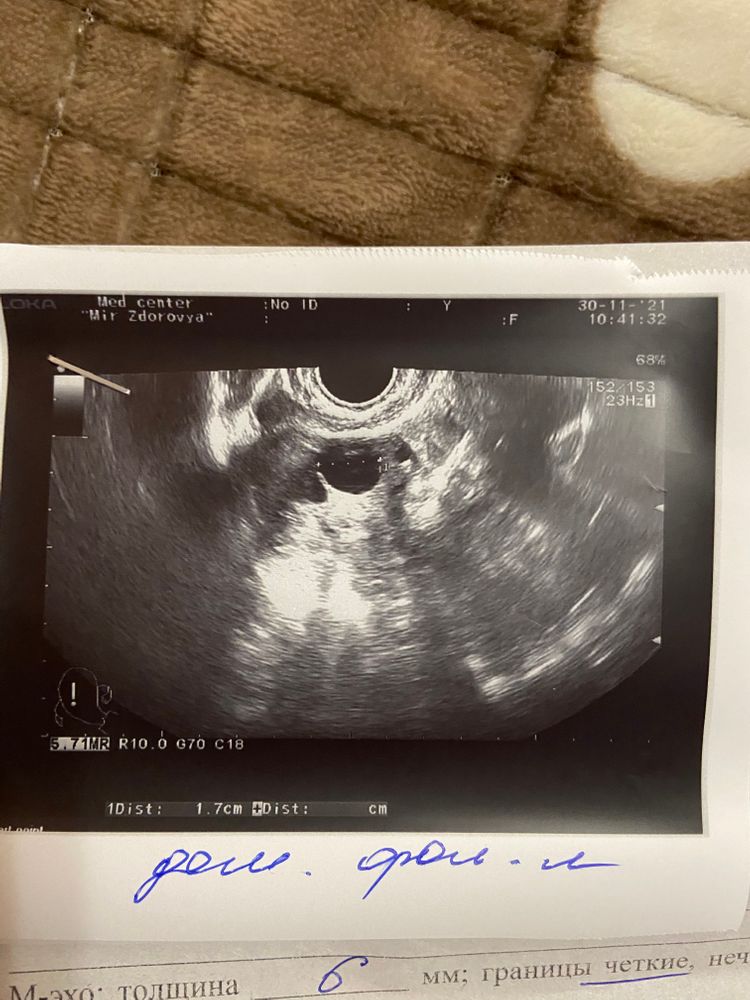

Ирина Ко в Зачатие 4 года Теперь спокойна Сегодня ходила на фолликулометрию, как переживания были по поводу этого Врач успокоил, на 12 дц фолликул составляет 17 мм , овуляция будет! 😀 Посмотрите еще 20 записей на эту тему Отменить Ответить 17-гидроксипрогестерон повышен , что с ним делать? Ростов-на-Дону Чаты Беременных Выберите чат: Январята-2026 Февралята-2026 Мартята-2026 Апрелята-2026 Майчата-2026 Июнята-2026 Июлята-2026 Августята-2026